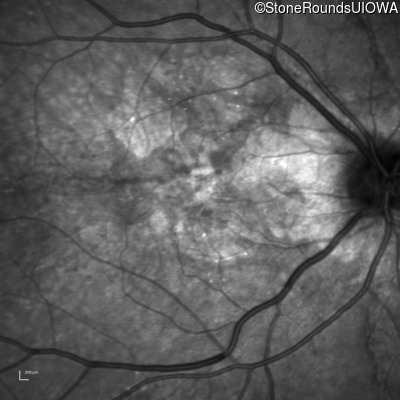

Infrared Fundus Photograph - Right - 20/25 +1

Exemplar

Infrared Fundus Photograph - Left - 20/25 +3